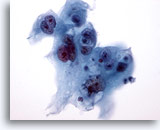

画像 1

肺FNA、単純ヘルペスウイルス肺感染症

多核化、核の相互圧排、スリガラス様クロマチンのほか、好酸性の核内封入体などウイルス性細胞変性に特徴的な様相が認められます。

60倍

画像 1

肺FNA、単純ヘルペスウイルス肺感染症

多核化、核の相互圧排、スリガラス様クロマチンのほか、好酸性の核内封入体などウイルス性細胞変性に特徴的な様相が認められます。

60倍